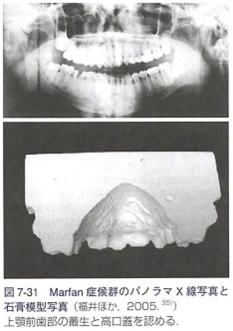

4:マルファン症候群と歯科医療

(1)歯科的特徴

高口蓋、不正咬合、狭窄歯列弓、口蓋裂・口唇裂,

歯の形態異常や形成異常、など.

上顎の餓蝕罹患率や顎関節症の頻度が高い.